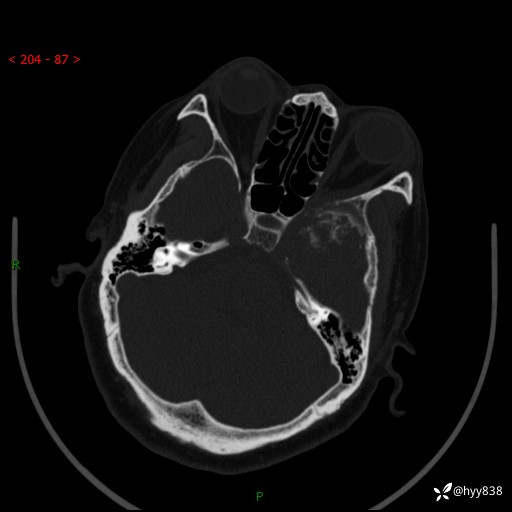

颅脑CT平扫